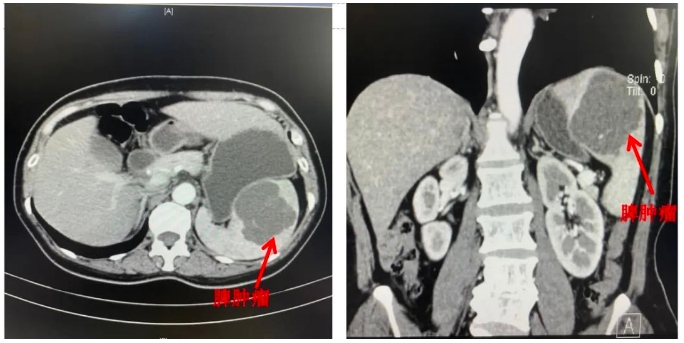

来自福清的林女士,10余年前在体检时发现脾脏囊性肿瘤,当初肿瘤仅2cm左右,但每年的定期体检都发现肿瘤在变大,到今年复查时,肿瘤最大直径接近10cm。辗转多家医院,医生均建议行脾切除术。想到要做器官切除,林女士一时心里无法接受。

日前,林女士前往我院肝胆胰外科邱福南主任医师的门诊,经验丰富的邱主任阅片后认为,肿瘤虽大,但主要在脾上级,是保脾手术的适应症。听到这句话,林女士悬着的心总算放下。